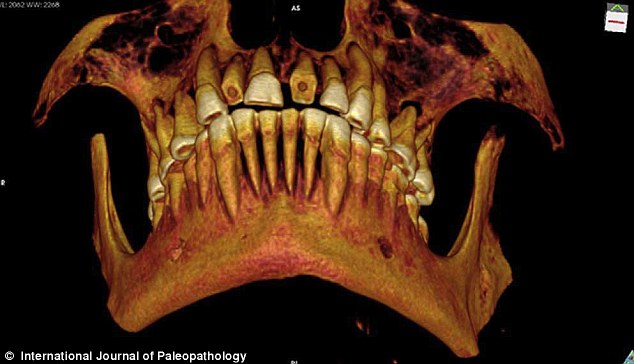

The ancient Egyptians, it seems, were particularly prone to the maladies of the mouth. In 2012, anthropologists at the University of Zurich examined over 3,000 Egyptian mummies and found that 18 percent showed evidence of dental woes of some kind.[11] This may have been owing to their diet of coarse grains that aggressively wore down teeth. Unfortunately, scant evidence has been found of “dental interventions” in ancient Egypt, one of the few being a cavity packed with linen discovered in an Egyptian mummy about 2,100 years old.[12] Although the Egyptians did develop their own brand of toothpaste, it clearly had limited effect and pain seems to have been a significant and ongoing dental problem. In A History of Dentistry (published in 1909), author Vincenzo Guerini included recipes found on ancient papyri that Egyptians used to ease toothaches and other dental maladies. One of these recipes involved making a mash of beans, dough, honey, green lead and verdigris, while other remedies involved pastes made from fennel seeds, olive oil, onion, cow’s milk, fresh dates, cake…a feast of medicines that, in all likelihood, just increased the patient’s agony.[13]